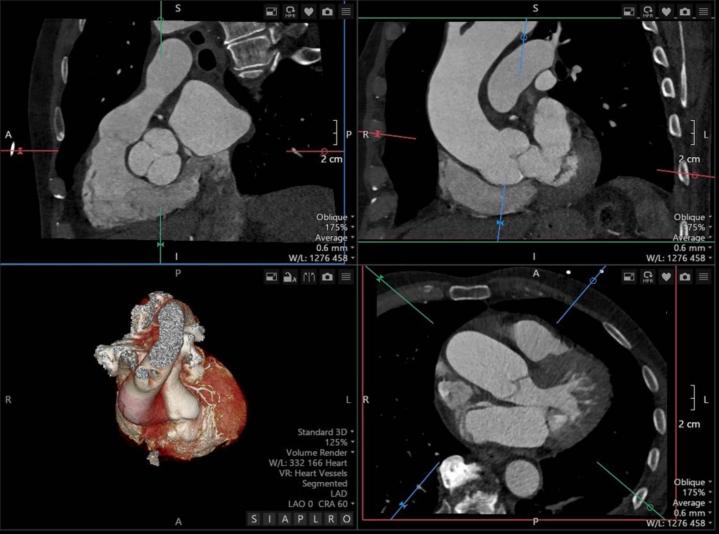

A man in his 70s presented with acute cerebellar stroke, breathlessness, and profound hypoxia worsened by the upright position. He tested positive for COVID-19, and computed tomography demonstrated a small pulmonary embolism, aorta dilation, and steep aortic angulation. Transthoracic echocardiography with a bubble study confirmed the presence of a PFO with right-to-left shunting during the Valsalva maneuver. Percutaneous PFO closure resulted in clinical improvement and resolution of hypoxemia.

This case highlights the interplay of PFO, aortic dilatation, and aortic angulation as key contributors to POS. Multimodal imaging is crucial for diagnosis and management.

一名70多岁男性因急性小脑卒中来诊,伴有呼吸困难,且直立位时严重低氧血症加重。他的新冠病毒检测呈阳性,计算机断层扫描显示有小的肺栓塞、主动脉扩张和严重的主动脉成角。经胸超声心动图造影检查证实存在PFO,在瓦尔萨尔瓦动作时存在右向左分流。经皮PFO封堵术使临床症状改善且低氧血症得到缓解。

该病例突出了PFO、主动脉扩张和主动脉成角之间的相互作用是POS的关键促成因素。多模态成像对于诊断和管理至关重要。